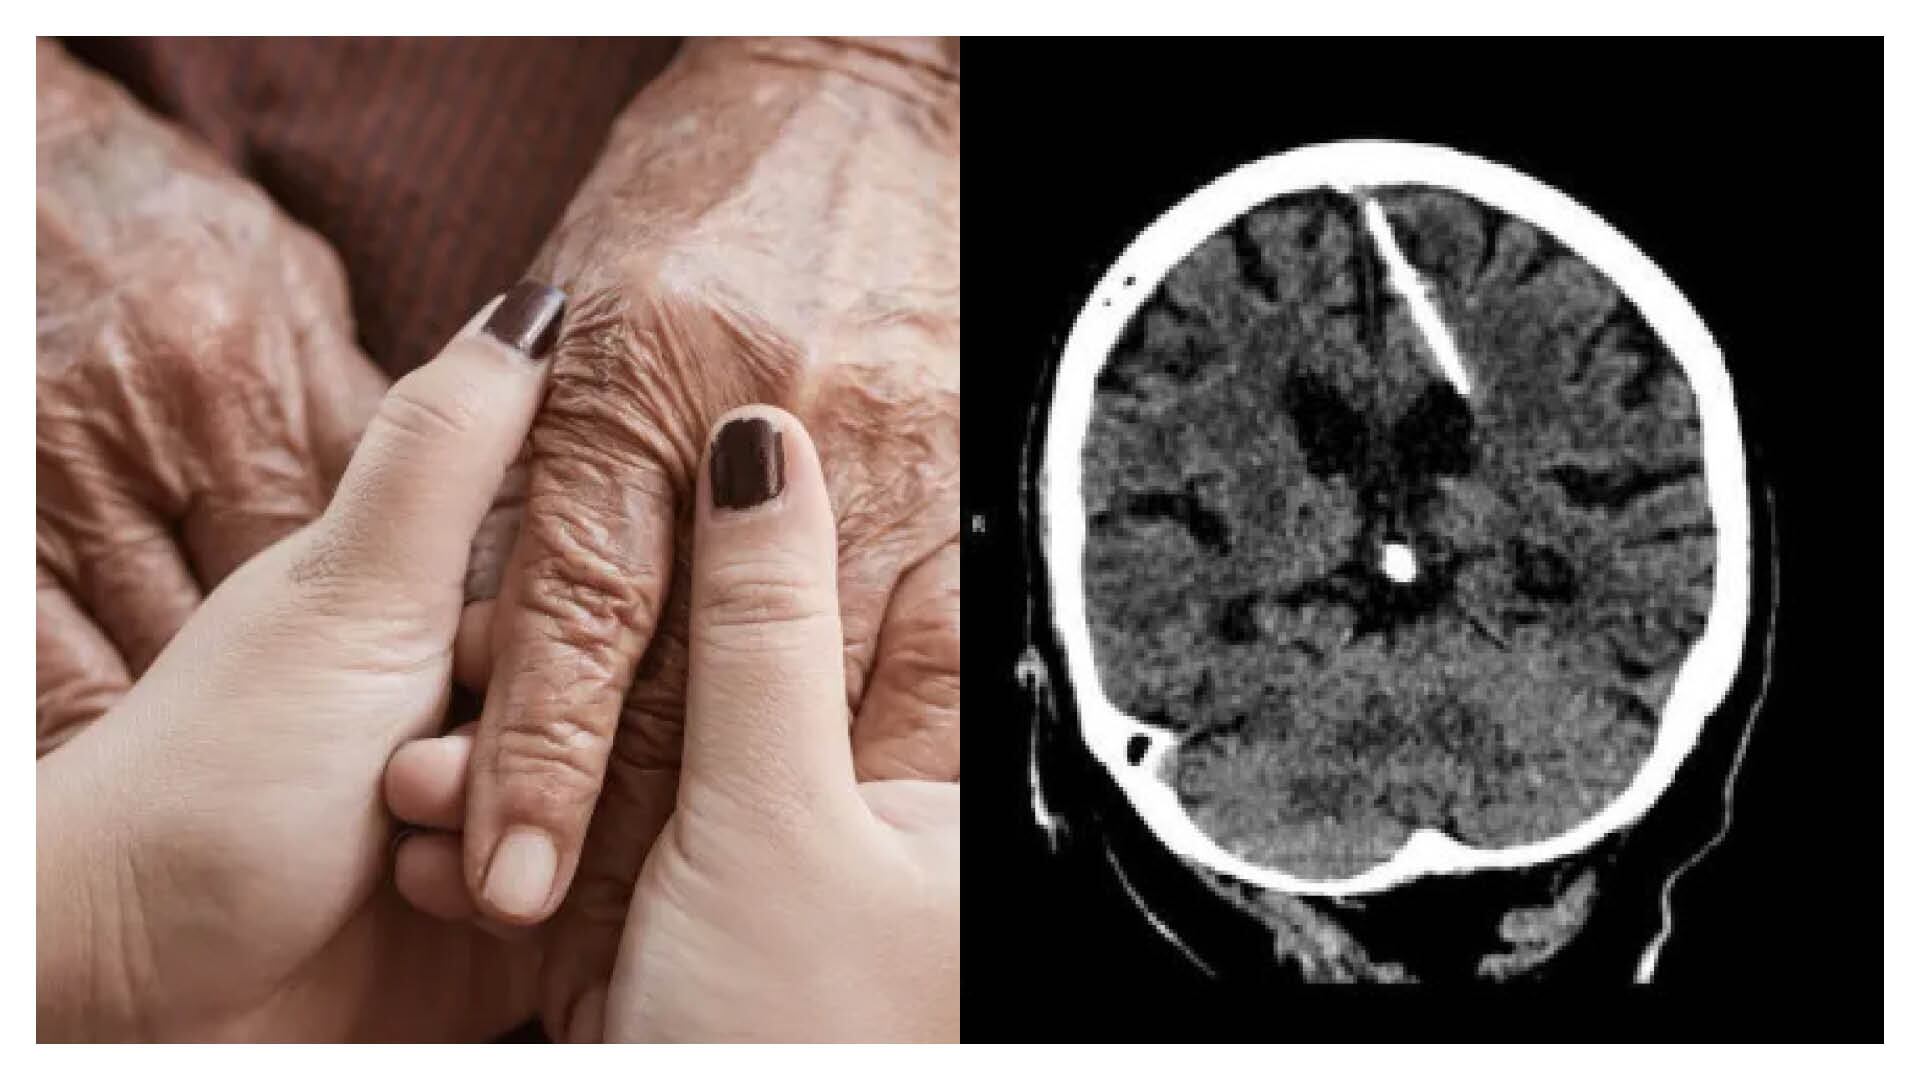

El pasado 4 de octubre del 2023 ocurrió un caso sin precedentes, pues médicos encontraron de manera accidental una aguja en el cerebro de una anciana al realizarle una tomografía computarizada.

El Ministerio de Sanidad de la región de Sajalín, perteneciente a un isla rusa en el mar de Ojotsk, reportó recientemente un caso particular y para nada común en la región. Una anciana que fue a tratarse a un centro médico descubrió que llevaba incrustada una aguja en el cerebro gracias a una tomografía computarizada que le practicaron en la unidad.

Todavía no se conoce qué llevó a la mujer a acudir al hospital, pero sí se sabe que ella no tenía conocimiento de portar ese cuerpo extraño en su cabeza. La exploración por TAC reveló accidentalmente una aguja de tres centímetros clavada en el lóbulo parietal izquierdo de la paciente.

Contra todos los pronósticos, esto no tuvo consecuencias negativas en la salud de la mujer, pues nunca sufrió de dolores de cabeza. “La salud de la paciente no corre peligro, su estado está bajo control del médico tratante. Se decidió no someterse a una cirugía, ya que esto sólo podría empeorar su condición”, informó la entidad a través de su canal oficial de Telegram.

Así, cuando era bebé, la paciente fue sometida a un mortal proceso a manos de sus progenitores. El procedimiento era el siguiente: “se insertaba una fina aguja en la fontanela del bebé, lo que dañaba el cerebro. La fontanela se cerraba rápidamente, ocultando las huellas del crimen, y el bebé perdía la vida”, explica el ministerio.

Sin embargo, la pequeña sobrevivió solo para encontrar 80 años después aquel objeto en su cerebro.